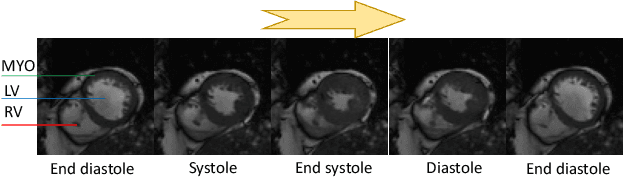

Abstract:Motion estimation of cardiac MRI videos is crucial for the evaluation of human heart anatomy and function. Recent researches show promising results with deep learning-based methods. In clinical deployment, however, they suffer dramatic performance drops due to mismatched distributions between training and testing datasets, commonly encountered in the clinical environment. On the other hand, it is arguably impossible to collect all representative datasets and to train a universal tracker before deployment. In this context, we proposed a novel fast online adaptive learning (FOAL) framework: an online gradient descent based optimizer that is optimized by a meta-learner. The meta-learner enables the online optimizer to perform a fast and robust adaptation. We evaluated our method through extensive experiments on two public clinical datasets. The results showed the superior performance of FOAL in accuracy compared to the offline-trained tracking method. On average, the FOAL took only $0.4$ second per video for online optimization.